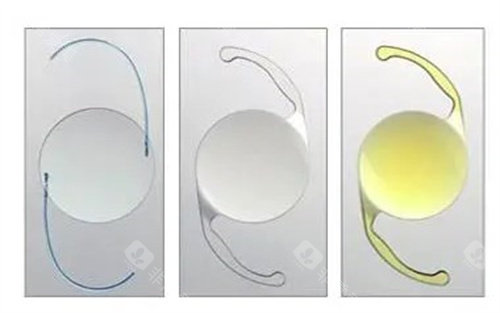

PRL晶体植入手术采用的是较高的技术和高品质的晶体材料。

这种晶体具有良好的生物相容性,能够与眼内组织协调共处,减少排异反应的发生。

这是因为PRL晶体植入手术是通过将定制的晶体植入眼内,直接改变眼睛的屈光状态,从而达到矫正视力的目的。